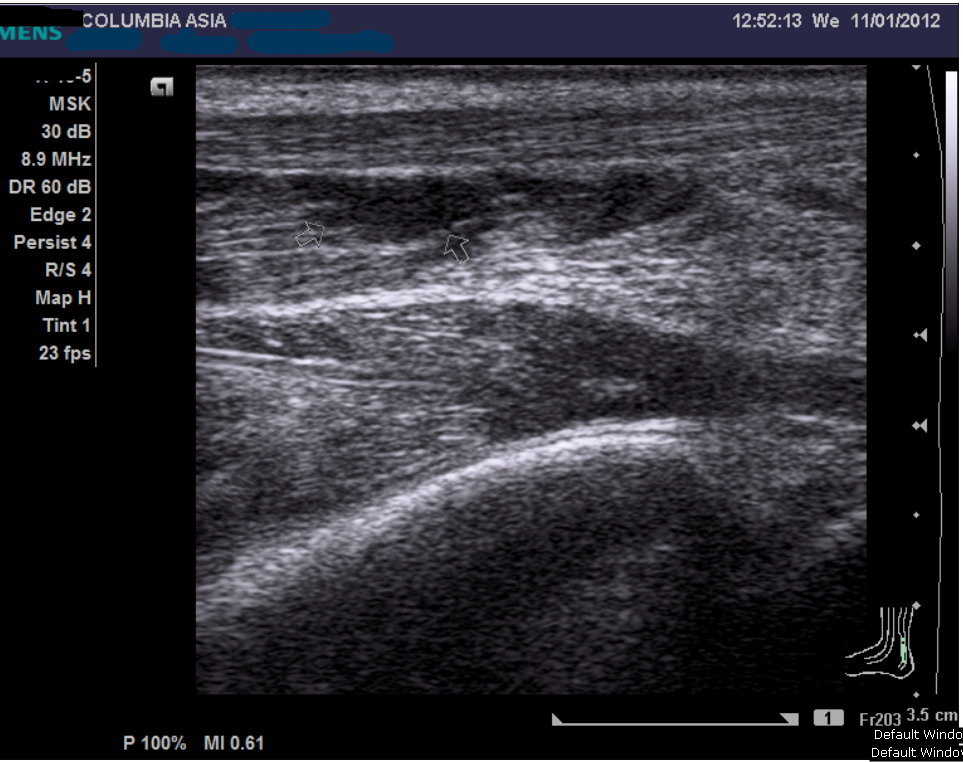

An ultrasound or MRI scan would help in this matter. I promptly sent him across the hallway to see the radiologist requesting for an ultrasound of his calf muscle, failing which we may proceed on to do a MRI scan.

The ultrasound report noted fluid/blood collection within the medial gastrocnemius (calf) muscle, which in the light of the patient’s history, confirmed the patient’s diagnosis:

Gastrocnemius muscle tear (calf tear)